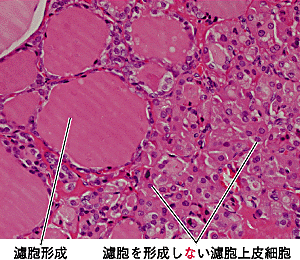

▲243ページ ミクロ写真3の書き込み(2009/11/20)

※ミクロ写真3の解説文も「濾胞上皮極細胞」ではなく,「濾胞上皮細胞」が正しい表記となります.